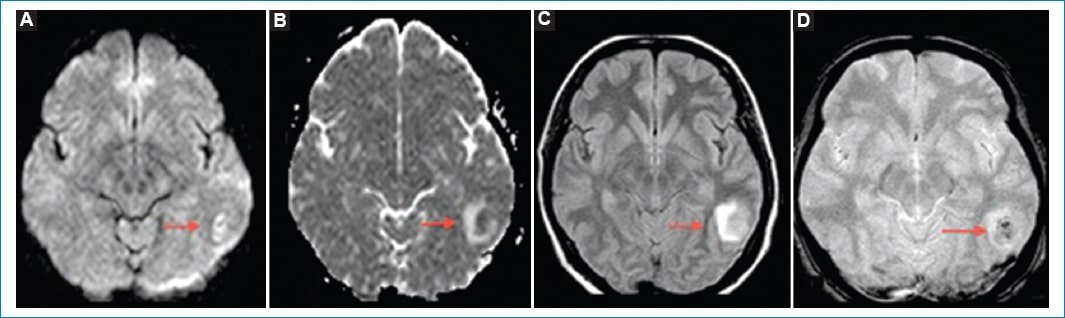

• Signos indirectos: los hallazgos en la RM son los mismos que en la TC, aunque más sensibles y específicos. Comprenden el infarto venoso que coexiste con edema cerebral vasogénico o citotóxico con o sin hemorragia intraparenquimatosa (Fig. 5)1820.

Figura 4. Trombosis venosa cerebral. Cortes coronales de RM en secuencia T1 con gadolinio A y B: Se identifica un defecto de relleno a nivel del seno venoso transverso del lado izquierdo que se extiende al seno sigmoideo homolateral (flechas). Dichos hallazgos se correlacionan con ausencia de señal de la estructura mencionada en la reconstrucción 3D de la angio-RM venosa (C y D).

Figura 5. Infarto venoso cerebral. Cortes axiales de RM. A nivel temporoparietal izquierdo (flechas) se identifica un aumento de señal heterogénea en la secuencia de difusión (A) que se corresponde con una leve hipointensidad en el mapa de ADC con halo hiperintenso (B). Dichos hallazgos son visibles en FLAIR (C) y en secuencia FFE (D), mencionando en esta última algunas áreas hipointensas en su interior vinculadas a áreas de sangrado.